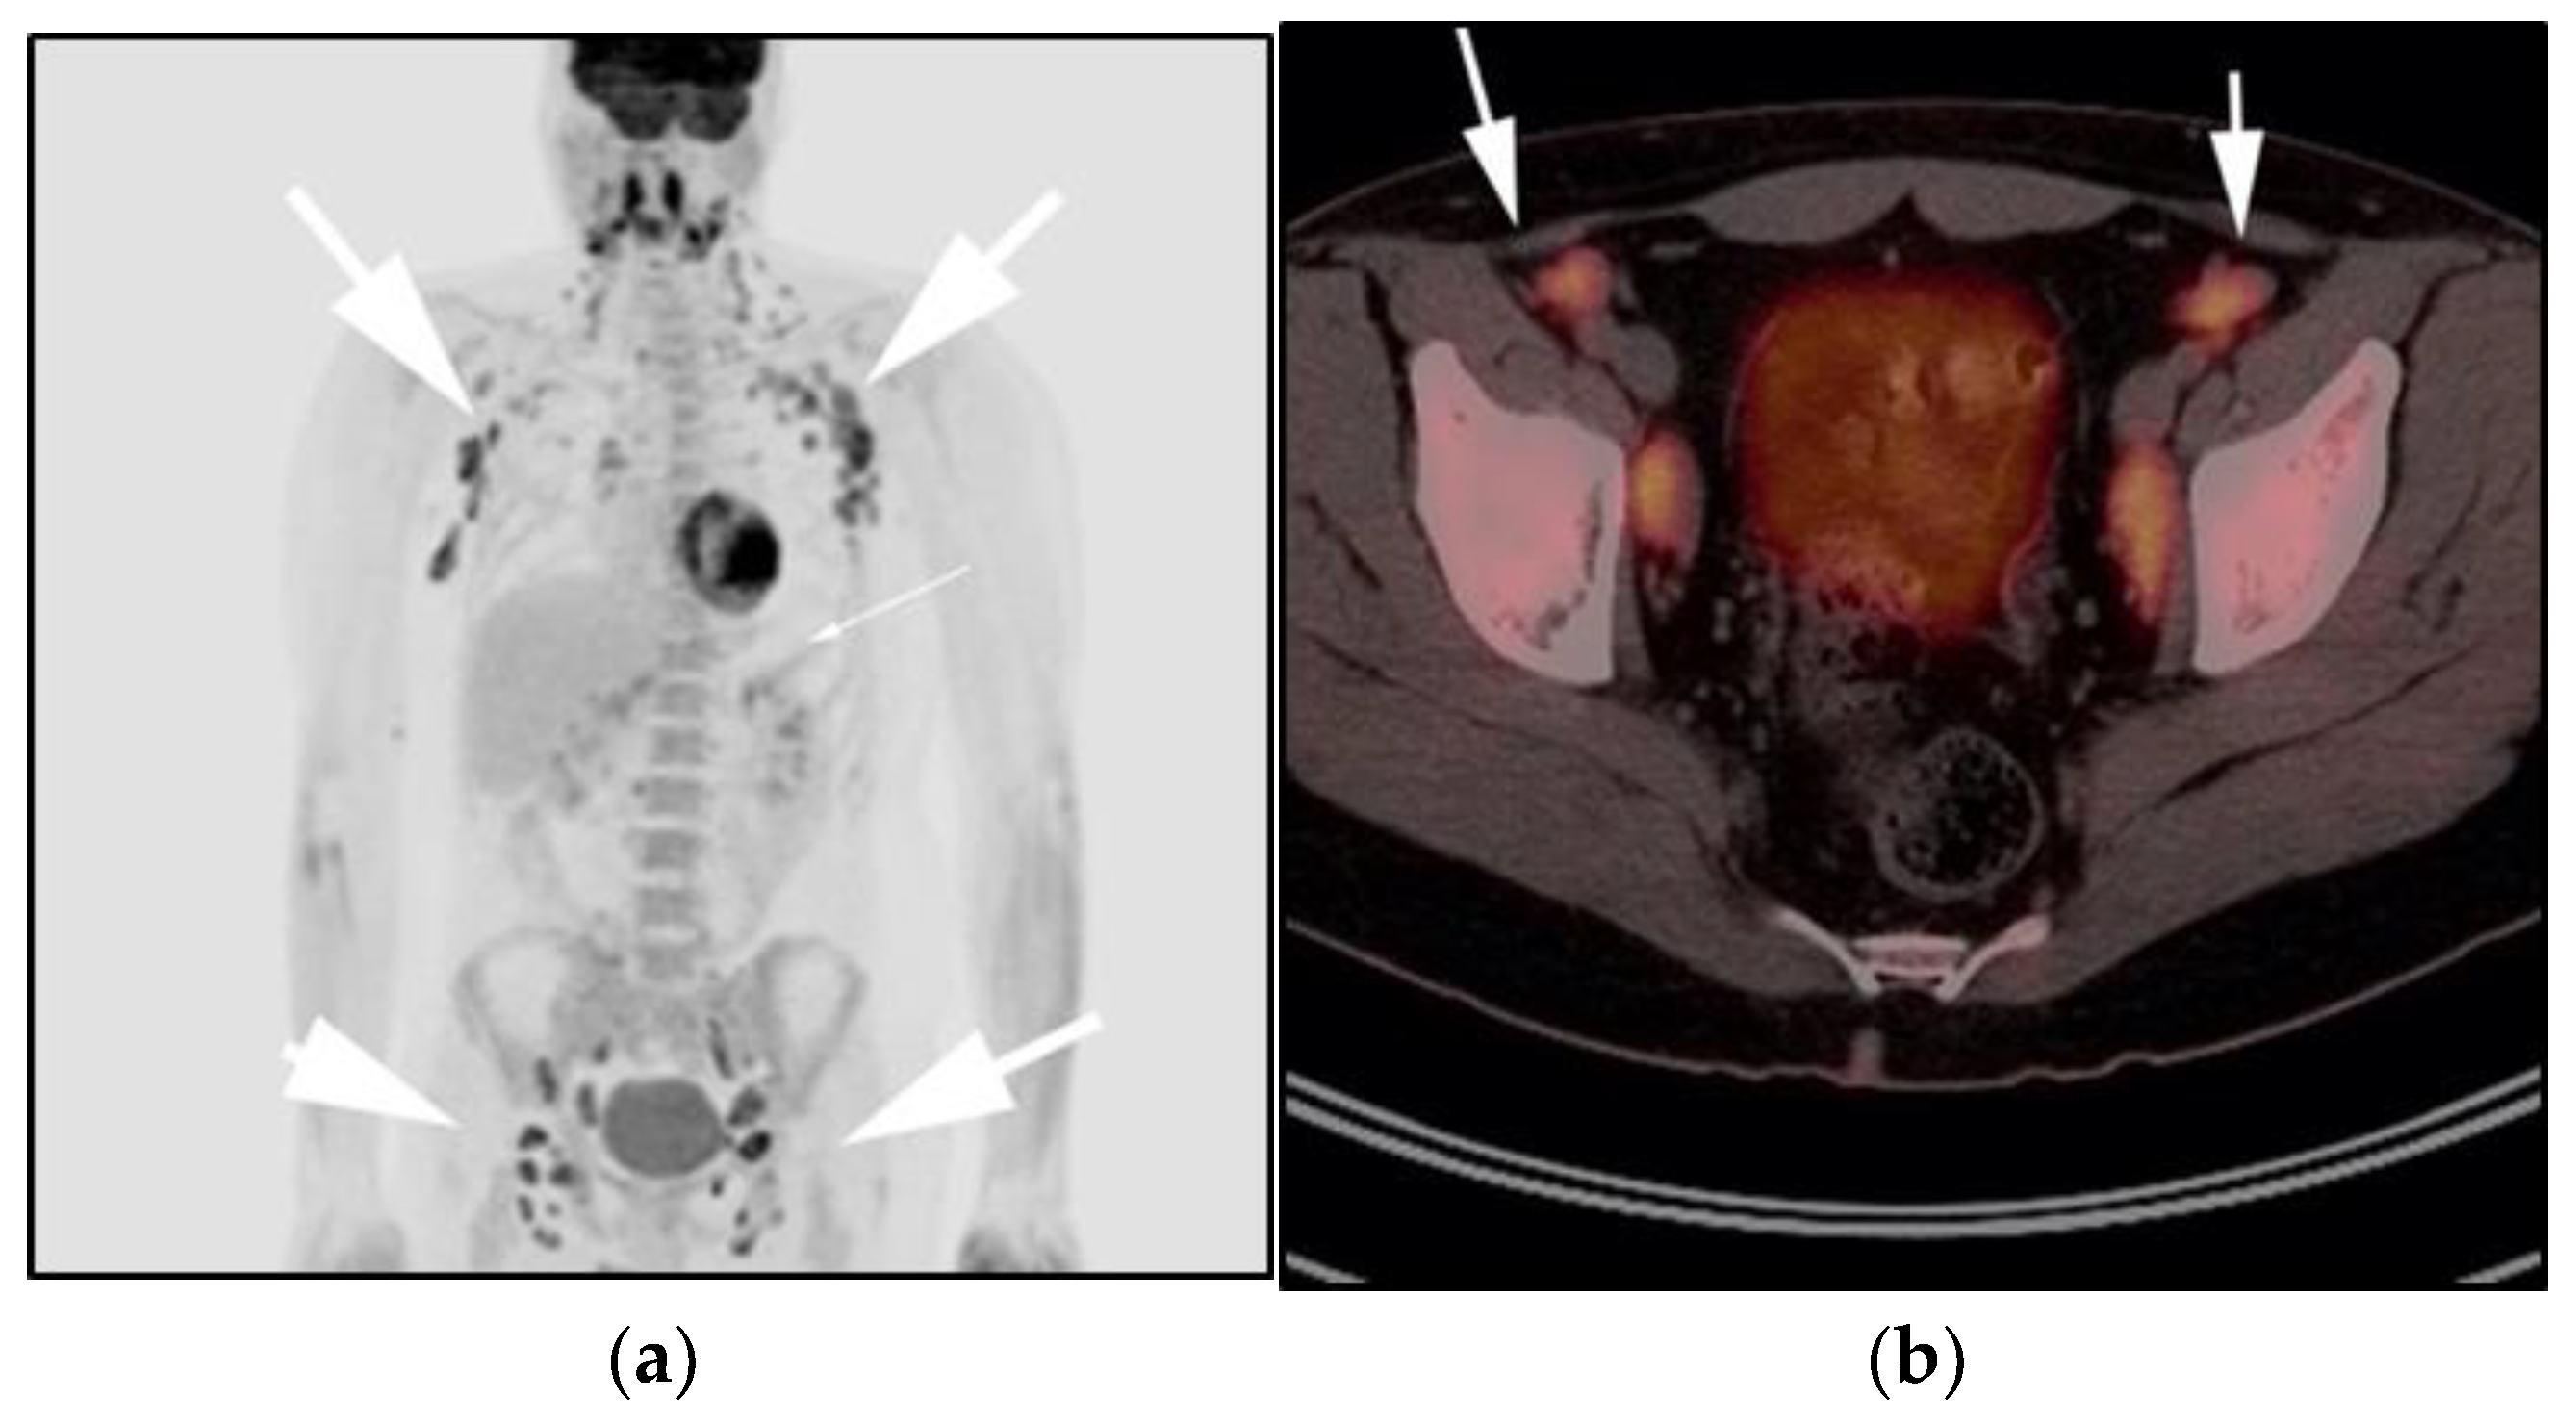

Figure 4.

A 30-year-old male with known history of autoimmune lymphoproliferative disorder since childhood. (a) Maximal intensity projection (MIP) FDG PET/CT image shows generalized hypermetabolic lymphadenopathy throughout the head, neck, chest, abdomen, and pelvis (white arrows). Note that splenic activity is not visualized (thin white arrow) because the spleen was surgically removed during childhood due to splenomegaly. (b) Axial FDG PET image shows hypermetabolic adenopathy within pelvis mainly about the bilateral pelvic side wall and external iliac nodes (white arrows). Lymph nodes often show little or only modest uptake, a clue, in addition to stability of nodal size and over multiple time points. Biopsy is the only method for definitive diagnosis. (c) H&E section of a lymph node shows highly proliferative paracortical expansion composed of small proliferative lymphocytes and immunoblasts with preserved lymphoid follicular architecture. There is sinus histiocytosis. (Original magnification 400×, H&E stain).

Once the diagnosis of ALPS is established, baseline and periodic follow-up CT scans should therefore be obtained to document the stability of lymphadenopathy and hepatosplenomegaly. 18F-FDG PET/CT may also be helpful because mild to moderate FDG uptake is typical of ALPS compared to the high FDG uptake characteristic of malignant lymphomas. By evaluating for areas of high FDG uptake, 18F-FDG PET/CT may help in the early detection of lymphoma transformation and demonstrate the best site for biopsy, when indicated [23]. Awareness of ALPS is pivotal because ALPS often requires long-term immunosuppressive therapies as opposed to chemotherapy that is standard for malignant lymphoproliferative disorders.